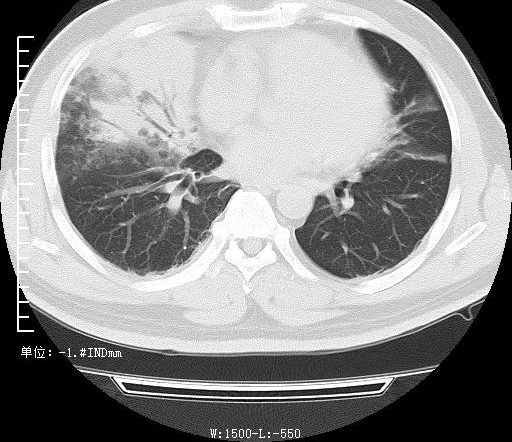

治疗前

被人紧急送往医院抢救,经检查,患者的氧分压59mmHg,正常人的数值在80 mmHg,且双肺CT照片提示有病变及实变。所幸经医师治疗,在肺灌洗、抗感染等综合对症治疗后,郑师傅的病情逐渐缓解,随后治愈成功即可出院。